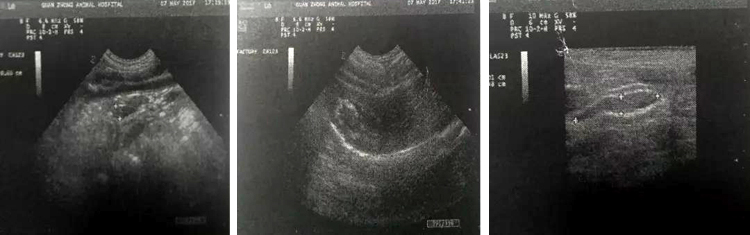

超声见:胆囊内见大量强回声光点,后方声影不明显;胆囊壁不光滑,厚度约0.3cm,周围回声光洁。结肠内大量积液腔约2.0cm,壁厚0.3cm,分层清晰。空肠、十二指肠壁分层清晰,结构良好,蠕动约20次/min。

印象:胆囊粘液囊肿、胆囊炎、急性肠炎。